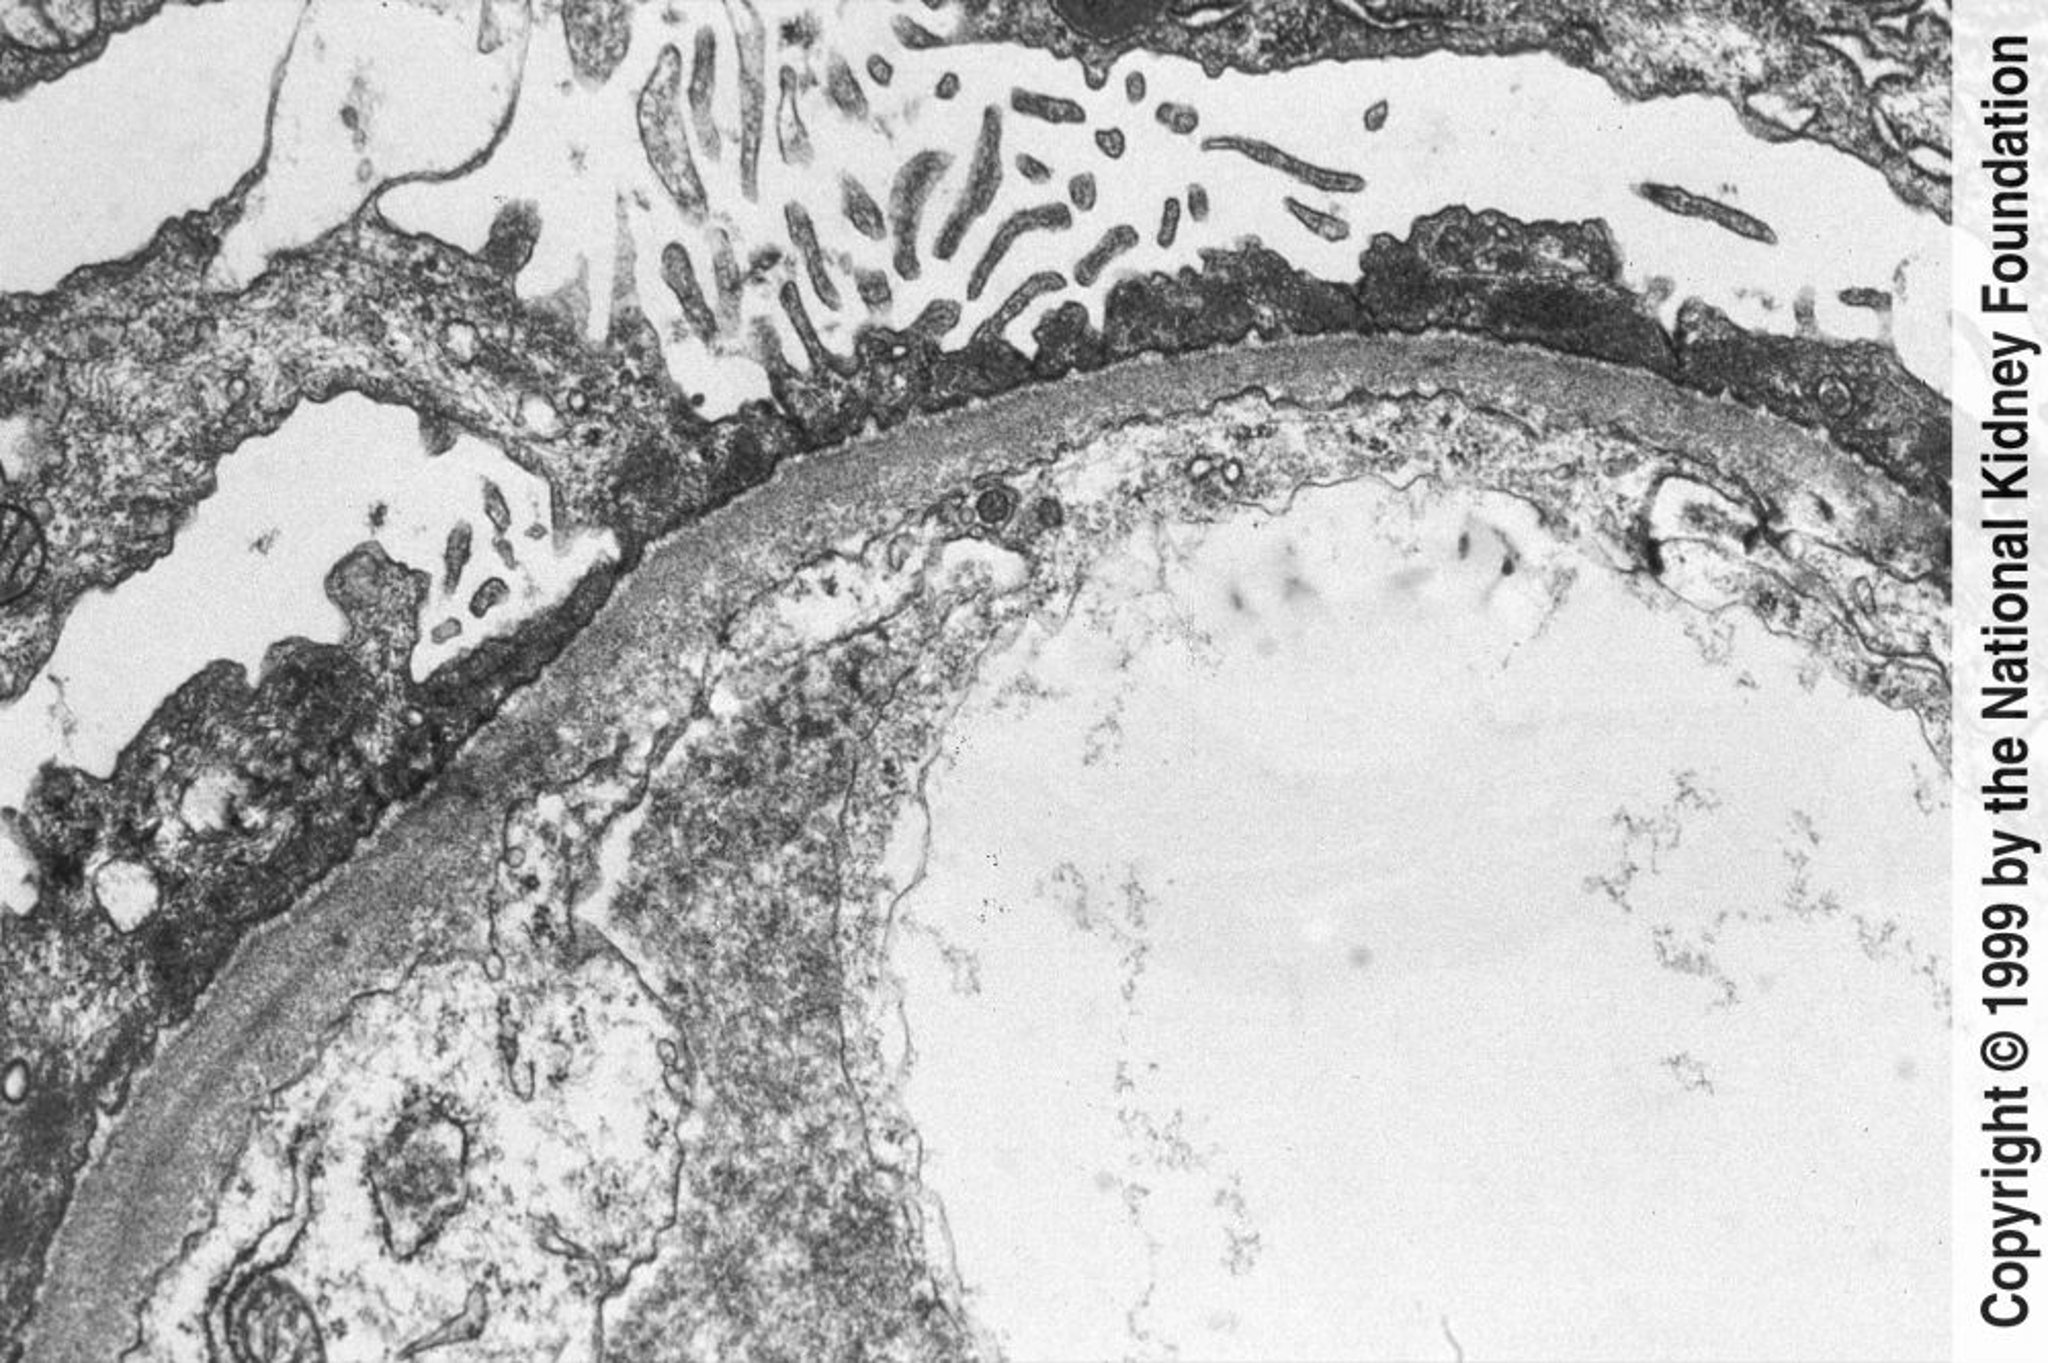

Болезнь минимальных изменений

Диффузное вымывание в астроцитарной отростке можно наблюдать в просвечивающем электронном микроскопе (×800).

Image provided by Agnes Fogo, MD, and the American Journal of Kidney Diseases' Atlas of Renal Pathology (see www.ajkd.org).